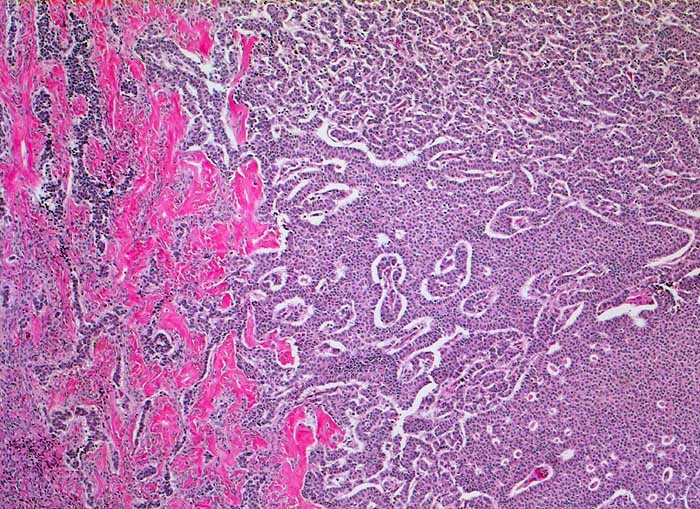

PathoPic ID 5300 - Granulosazelltumor vom adulten Typ

Granulosazelltumor vom adulten Typ

maligner Tumor

Ovar

Genitalorgane, weiblich

Teils trabekuläres, teils solides Wachstum mit zahlreichen

Call Exner Körperchen.

Die Tumorzellen zeigen eine Positivität für Inhibin und CD99, sind jedoch negativ für EMA.

Ovarial-Tumor links -> Adnexektomie links. Frage: Dignität? CA-125 im Normbereich.

Histologie

50

62